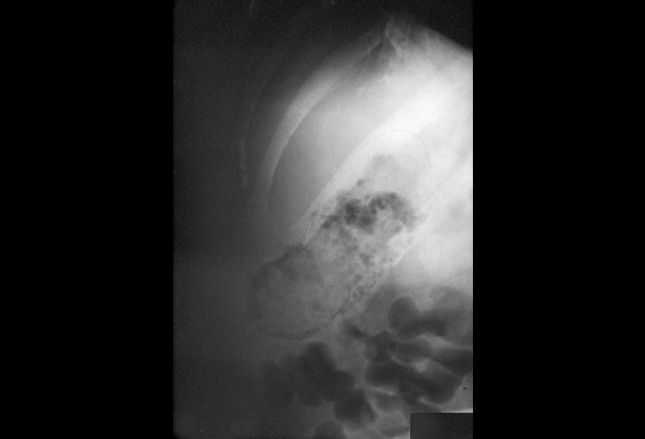

答案:B.食管穿孔(布尔哈夫综合征)

布尔哈夫综合征,食道全层穿孔,常在大量饮酒,突然、有力呕吐后发生。这一疾病有很高的死亡率,需要紧急外科会诊。

前图胸片显示泛影葡胺

对比材料泄露(短箭头)进入胸膜腔的左后外侧,说明食管穿孔(指向胃管的长、细箭头)。左侧胸腔积液

是布尔哈夫综合征患者最常见的影像学表现。这种综合征的疼痛通常是剧烈的,严重的,并且弥漫于腹部到颈部的所有位置。患者可以快速发生心动过速,呼吸急促及低血压,导致休克。也可发生纵隔炎;胸部听诊,能听到“Hamman crunch”(一种噼里啪啦的声音,与每次心跳相符合)。胸部CT研究通常能确定布尔哈夫综合征的诊断;也可能显示起源于食管的错误通道(箭头)。